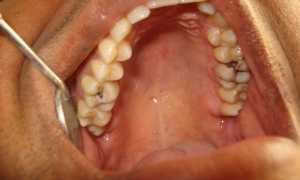

Фото до и после

Фото 2. Слева – фото до процедуры по удалению зуба, справа видны последствия – изменение прикуса.

Фото 3. На фото видны изменения, к которым привели зубы мудрости, при этом остальные начали сдвигаться, торчать в разные стороны.

Фото 4. На фото видно, что нижние зубы мудрости растут в неправильном положении, в такой ситуации один из резцов ушел внутрь челюсти.